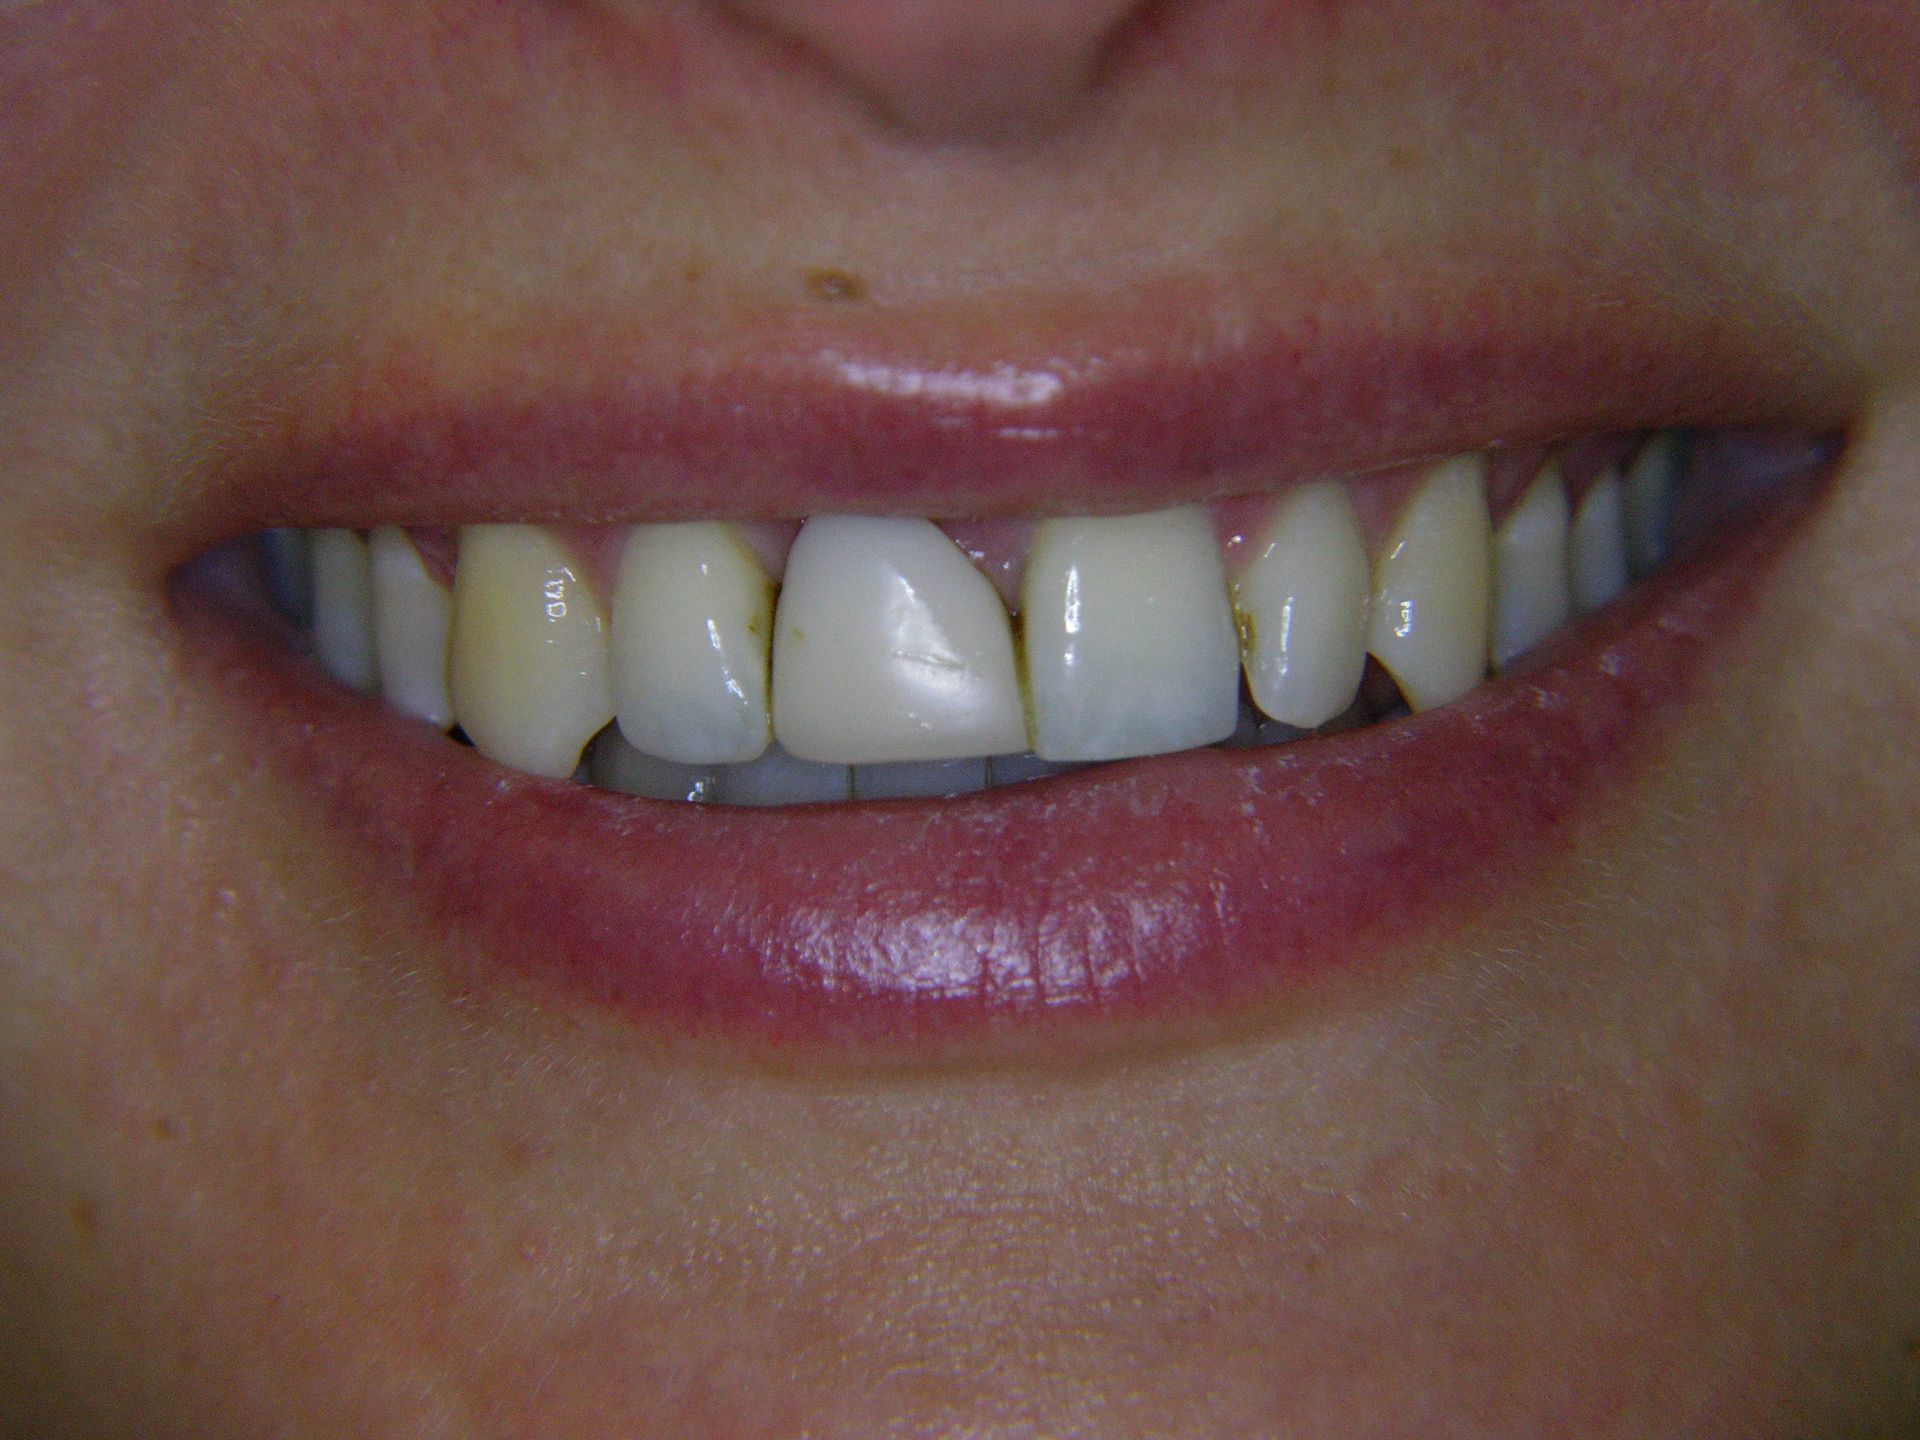

Beispiele von Versorgungen